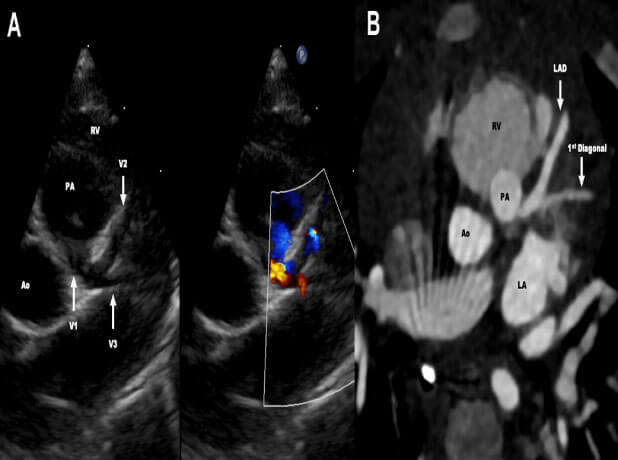

Anomalous Left Anterior Descending Coronary Artery With Retroaortic Left Circumflex Artery: A Novel Coronary Pattern

A novel coronary anatomy in the form of anomalous left anterior descending coronary artery from pulmonary artery with a retroaortic left circumflex arising from the right coronary artery is presented. This unreported anatomy was discovered in a 7-month-old girl with failure to thrive.